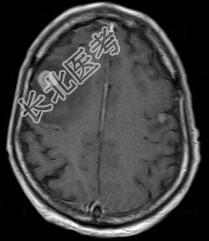

- 多项选择题大脑半球肿瘤(如图所示)的临床表现有 ( )

A、精神症状

B、癫痫发作

C、感觉障碍

D、运动障碍

E、视野缺损